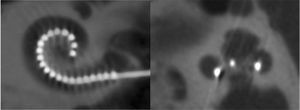

La inserción del haz de electrodos debe ser realizado de forma lenta y atendiendo a las resistencias. Las zonas de mayor problema o compromiso durante la inserción, en relación a la producción de lesiones y preservación de restos auditivos se localizan en dos áreas principalmente (Figura 6):

- 1.

Región correspondiente al final de la espira basal (8-12mm), en esta región que coincide con una profundidad de inserción de 140°-180°, existe el primer compromiso de espacio entra las dimensiones y orientación de la escala timpánica y el porta-electrodos. De aquí que ciertos estudios concernientes a la preservación de las estructuras cocleares, no exceden esta localización.

- 2.

Región por encima de los 400° de inserción, en este punto el compromiso de espacio es muy grande por lo que salvo en casos con diseños muy flexibles y estrechos de electrodos, es muy difícil no producir daño en las estructuras cocleares. La inserción de los electrodos activos se practica introduciendo el implante de 17 a 22mm.